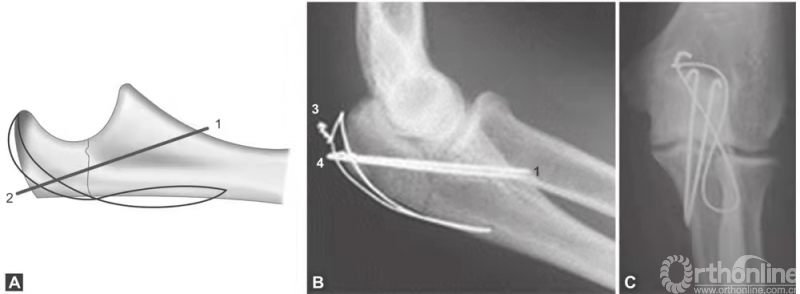

(图1A~C)为简单尺骨鹰嘴中部横形骨折,张力带钢丝可提供简单、便宜及有效的固定。

图1 A~C(1)克氏针应刚好只穿透前侧骨皮质;(2)张力带钢丝应放置在肱三头肌止点下方,在该部位打结,包埋;(3)张力带钢丝不应该在这里打结,因为它会导致皮肤损害和重度不适;(4)克氏针末端应在这里剪断,折弯并包埋

Weber -Vasey技术改良方法很多,有两个特别有用。一是使用长克氏针,到达尺骨髓腔的远端。尺骨髓腔的自然弯曲为直克氏针提供了可靠的三点固定,产生摩擦力,防止克氏针退出。二是克氏针贯通冠状突稍远端尺骨前侧皮质(图1A~C),使用该方法时,克氏针不得超过前侧骨皮质2~3mm,否则可能损害前侧的神经血管。两个方法中,近端克氏针和钢丝都必须很好地弯曲并包埋在鹰嘴尖端,以防止造成损害。